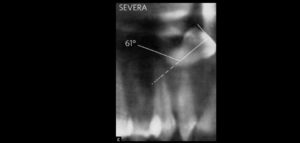

86 – Exactitud de los diferentes tipos de diseño de las guías quirúrgicas en la colocación de implantes

El número de pacientes que requieren prótesis sobre implantes ha aumentado considerablemente en los últimos años. La osteointegración de los implantes dentales es el requisito